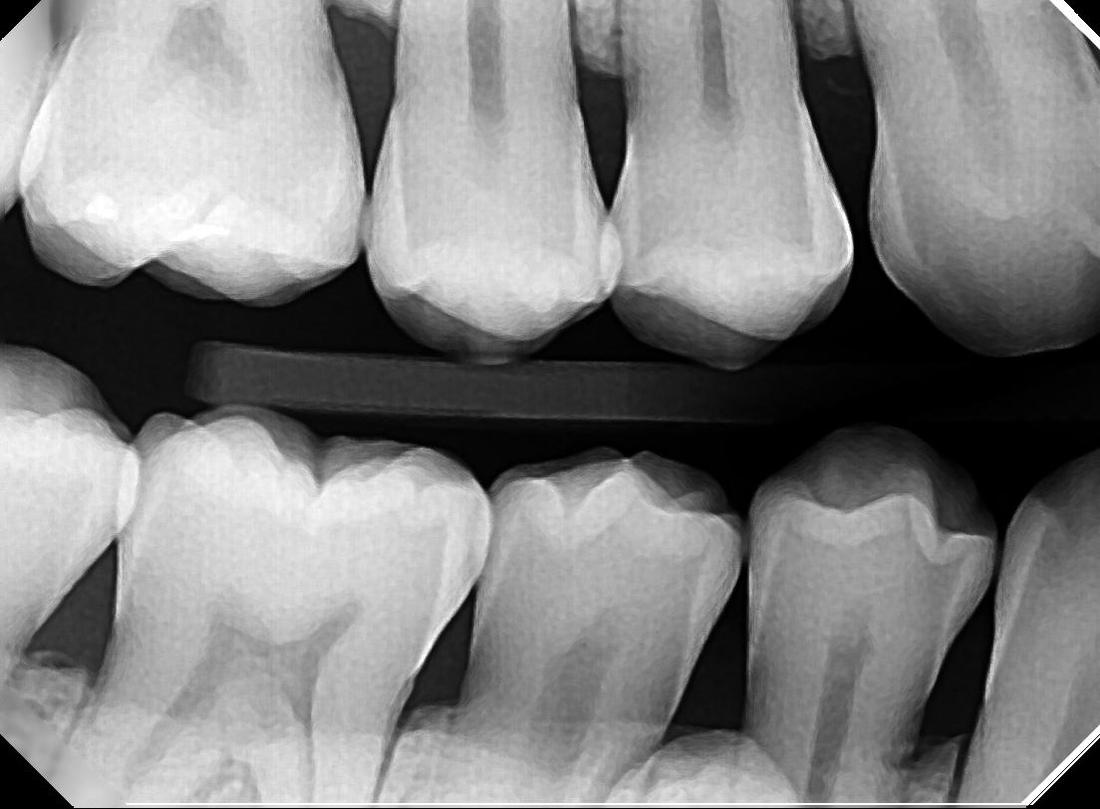

Do you see some white stuff in yellow circles stuck between your teeth?

You may be confused you could just get regular cleaning for these build-ups. You will need gum treatment or Scaling and Root Planning to remove all these for healthy gum!